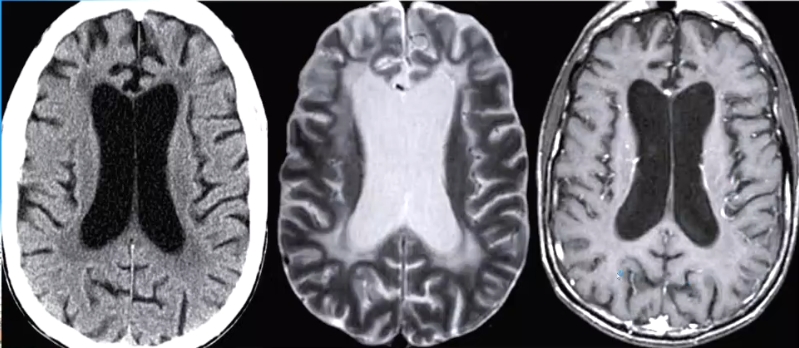

影像表现

1. 脑室周围白质弥漫性脱髓鞘,不强化、无占位效应

2. 脑萎缩√鉴别:PML(进行性多灶性脑白质病)